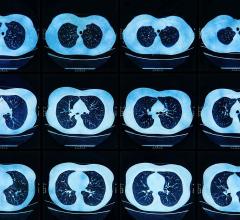

January 30, 2023 — Photon-counting detector CT reduces the amount of contrast needed for CT angiography (CTA) while ...